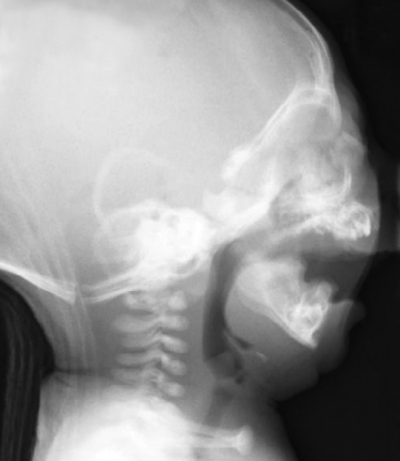

生後1か月の乳児。哺乳障害がみられたため、小児科からの紹介で来院した。出生直後から仰臥位で吸気時の喘鳴とチアノーゼがみられるという。初診時の側貌写真、口腔内写真及び頭部側方向エックス線写真を別に示す。

考えられる疾患はどれか。1つ選べ。

d. Robin シークエンス